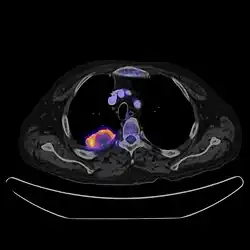

Positron emission tomography–computed tomography is a hybrid CT modality which combines, in a single gantry, a positron emission tomography (PET) scanner and an x-ray computed tomography scanner, to acquire sequential images from both devices in the same session, which are combined into a single superposed (co-registered) image. Thus, functional imaging obtained by PET, which depicts the spatial distribution of metabolic or biochemical activity in the body can be more precisely aligned or correlated with anatomic imaging obtained by CT scanning.[41] PET-CT gives both anatomical and functional details of an organ under examination and is helpful in detecting different type of cancers.[42][43] Hybrid PET-CT systems have become more effective with the integration of anatomical details from CT scans. This integration allows for the creation of an attenuation correction map, which helps refine PET images. These advancements have notably reduced examination duration, increased diagnostic accuracy, and instilled greater confidence in the accuracy of diagnoses.[44][45] In oncology, studies show that using PET-CT together is better for accurately staging and restaging than using CT or PET alone.[46][47][48]